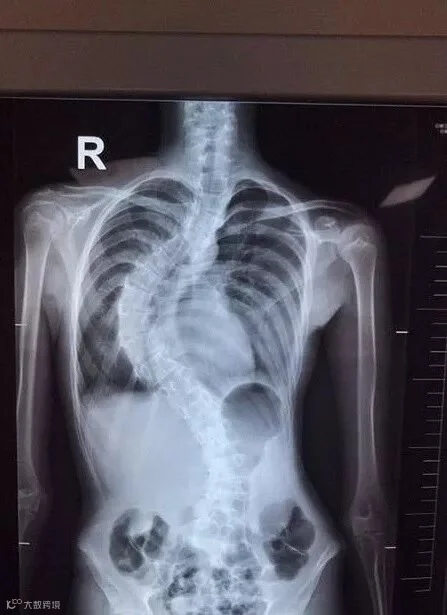

正常人的脊柱从后面看应该是一条直线,并且躯干两侧对称,而12岁的珠海姑娘小玲脊柱却如扭麻花一般变成左右 “S型”,弯度最高达87度,高低肩、直不起腰、剧烈活动后呼吸困难……日前,珠海市中西医结合医院骨二科成功开展市内首例严重青少年特发性胸腰椎脊柱侧弯矫正术,经过治疗小玲终于能挺直腰杆。

10度、35度、60度、80度……短短一年多的时间,小玲病情迅速发展,她的脊椎越来越弯,背部向一侧弯曲越来越严重,像一个大写的“S”,走路负担越来越重直不起腰、呼吸也急促困难。

“青春期是快速生长发育阶段,因此小玲的侧弯畸形发展很快。如不及时纠正治疗将影响到患者的心肺功能和脊髓神经,甚至严重者造成截瘫。”珠海市中西医结合医院骨二科主任彭鹏介绍,“由于小玲的侧弯角度较大且进展迅速,通过佩戴支具等保守治疗已经难以有效控制病情,为小玲根治病痛的办法,只有手术。”

人体脊柱周围存在有大量重要的血管和复杂的神经系统,一旦造成损伤,很可能导致患者瘫痪、甚至死亡。所以手术必须认真和精准,不能有一丝马虎。彭鹏说,“手术经历了总共9个多小时后终于顺利完成!小玲扭转畸形的脊柱变成了一条直线,小姑娘的脊柱不仅成功‘直立’了,肺功能也得到明显改善,身高瞬间增高了5cm!”